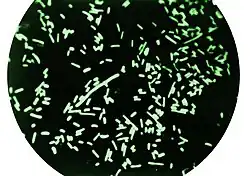

| Dark-field microscopy revealing Shigella dysenteriae bacteria | |

Shigella dysenteriae is a species of the rod-shaped bacterial genus Shigella.[1] Shigella species can cause shigellosis (bacillary dysentery). Shigellae are Gram-negative, non-spore-forming, facultatively anaerobic, nonmotile bacteria.[2] S. dysenteriae has the ability to invade and replicate in various species of epithelial cells and enterocytes.[3]